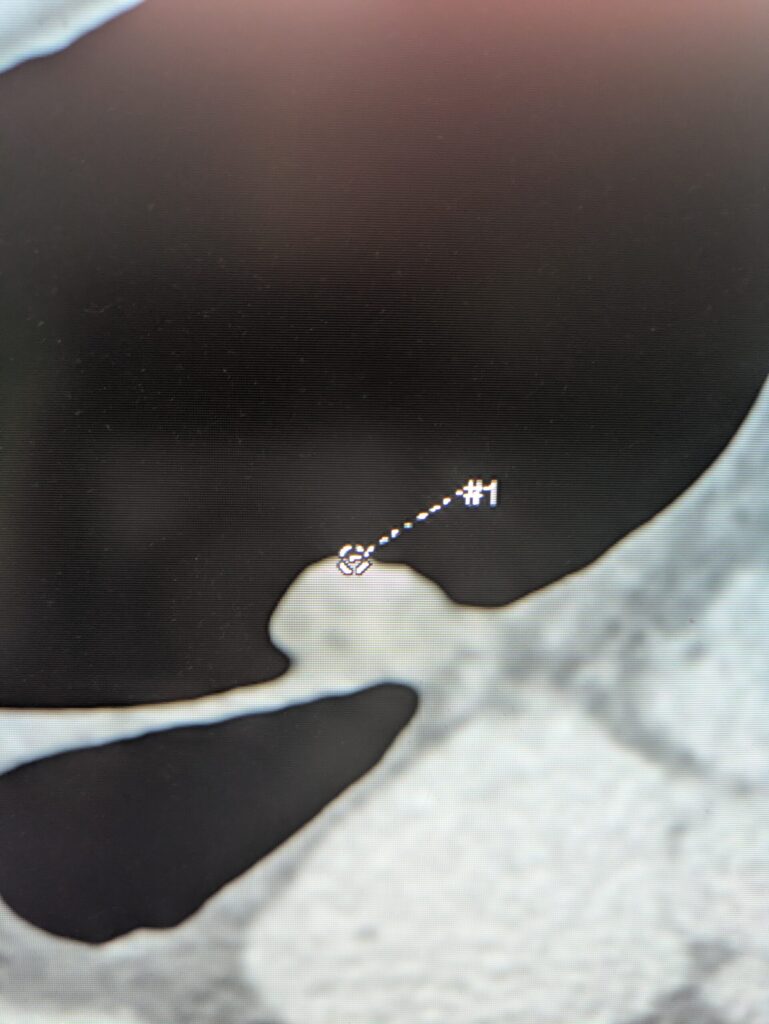

CTC uses CT scanning to create 3D images of the colon, allowing doctors to “virtually” inspect the inside without inserting a scope.

4. 3D images and maps are generated with software.